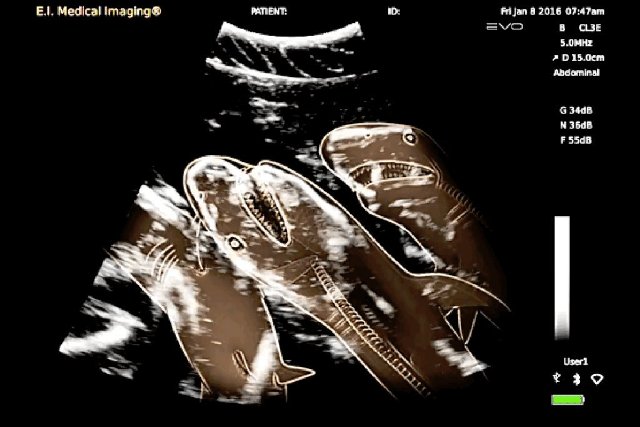

Մենք բոլորս լավ պատկերացնում ենք, թե ինչպես է անցնում մարդու հղիությունը, և շնորհիվ ժամանակակից տեխնոլոգիաների՝ կարող ենք տեսնել երեխային մայրիկի արգանդում հղիության ամենավաղ փուլում։ Իսկ ինչպե՞ս է ընթանում կենդանիների հղիությունը։ Մասնագետները, ովքեր հոգ են տանում հղի կենդանիների մասին, ներկայացրել են նրանց ռենտգենային և ուլտրաձայնային լուսանկարները, որոնք ձեր դատին է հանձնում «twizz.ru» կայքը։

Շնաձուկ